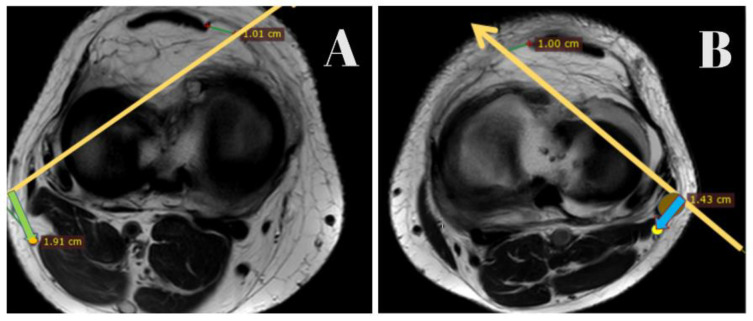

Methods: In this retrospective study, we examined MRI scans of 30 ACL-injured knees and 30 normal knees. A reference line was drawn 1 cm medial to the patellar tendon at the joint level, extending to the lateral margin of the popliteus and continuing posteriorly. Perpendicular distances from this line to the CPN were measured to compare anatomical variations between the groups. These measurements were analyzed using paired t-tests, with a p-value of less than 0.05, which is considered statistically significant.

Results: Analysis of 60 MRI scans revealed that the CPN is located significantly closer to the reference line in ACL-injured knees (mean distance: 1.59 cm) compared to normal knees (mean distance: 2.01 cm), with a p-value of less than 0.005. This finding suggests a higher potential risk of nerve injury in ACL-injured knees during inside-out meniscal repair procedures.